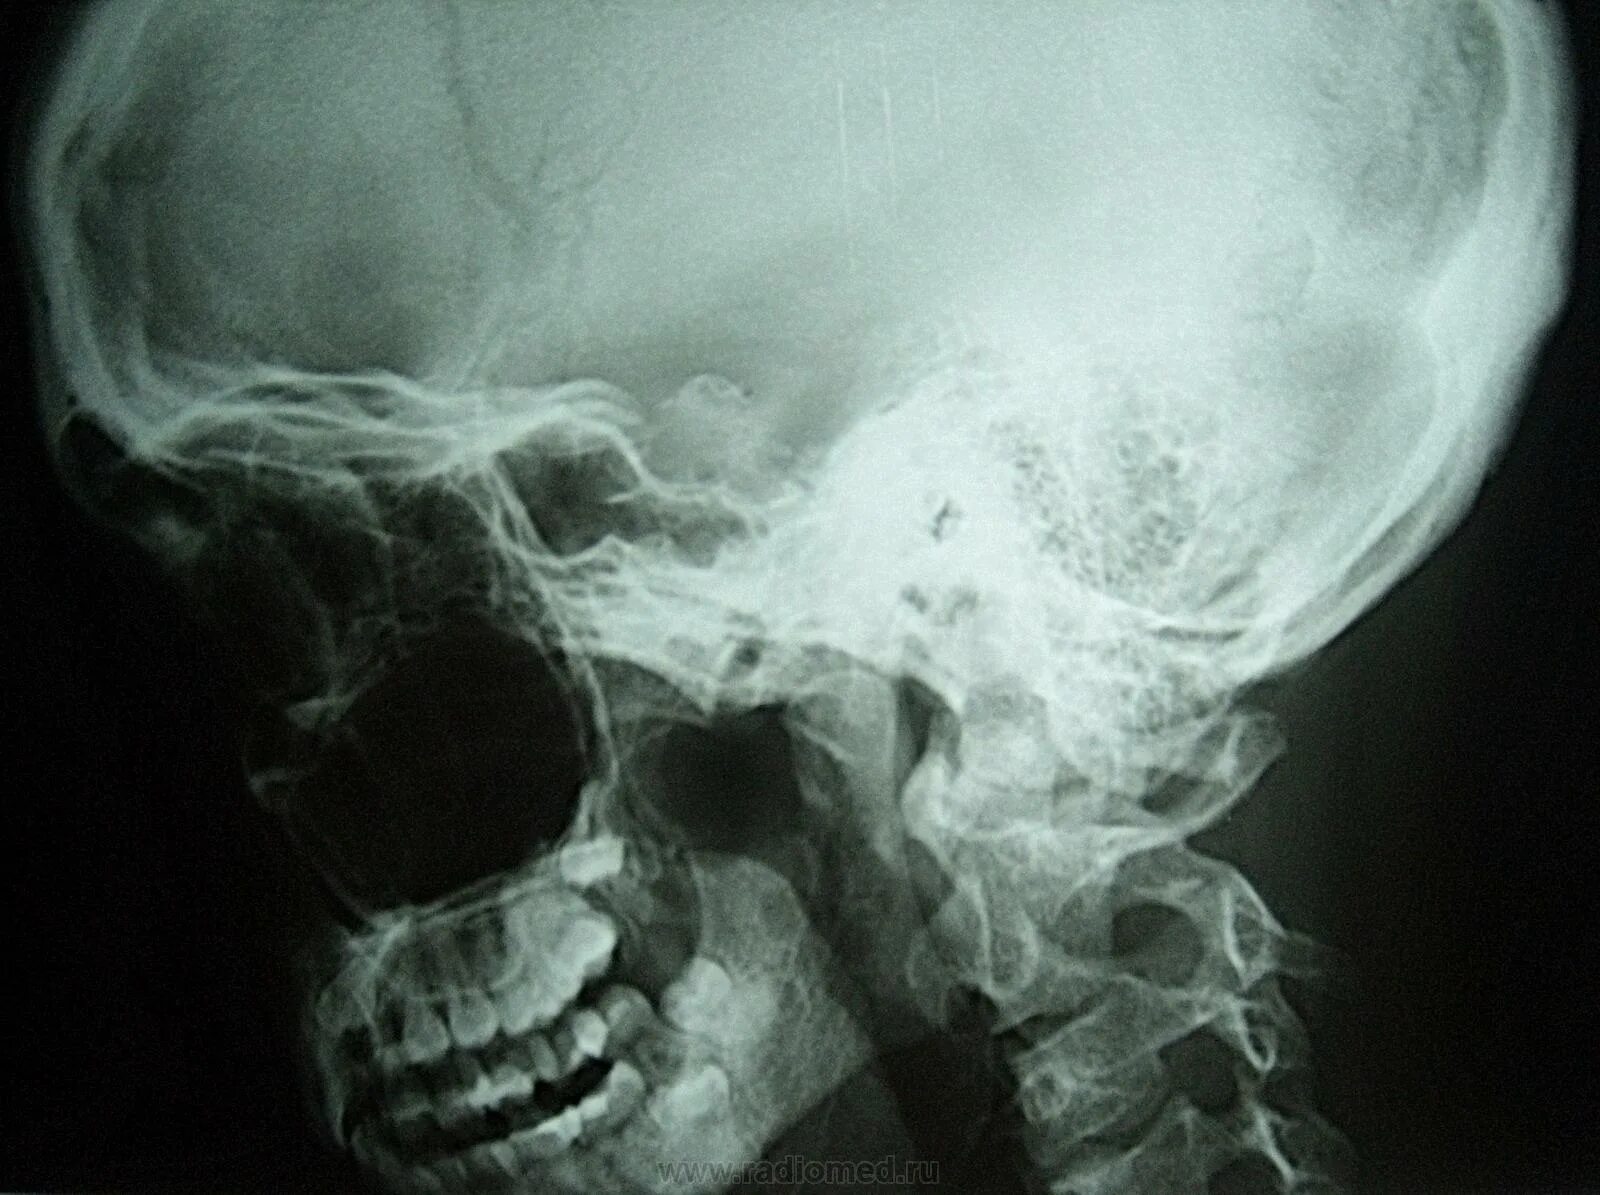

Киммерли что это такое у взрослых